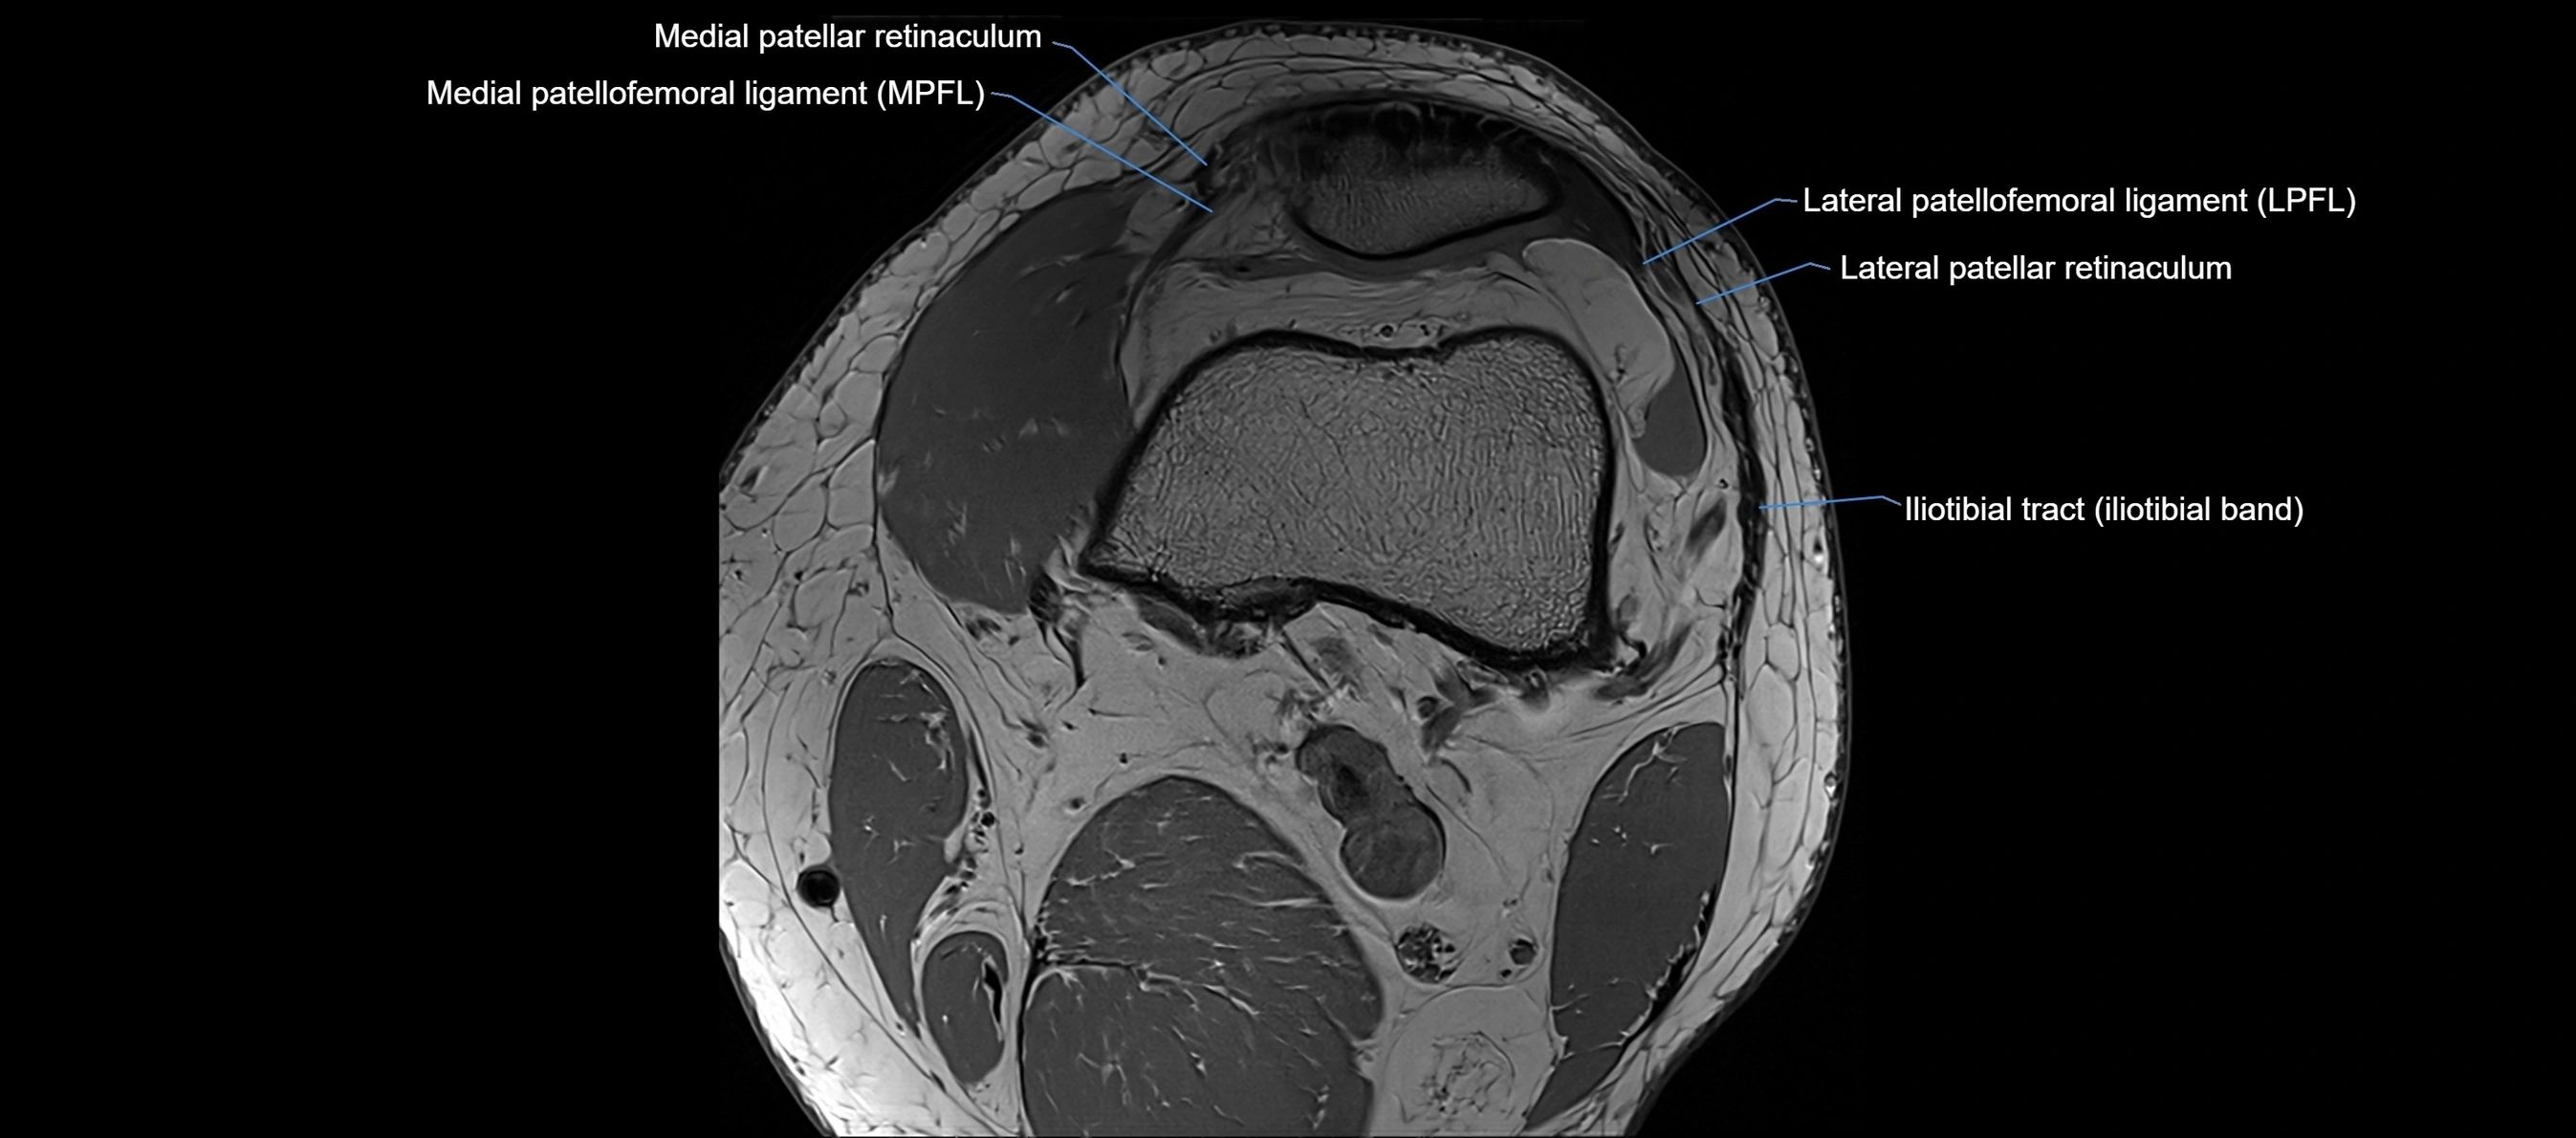

MRI Appearance

T1-weighted images:

• Normal ACL appears as a low-signal band-like structure crossing the intercondylar notch

• Surrounded by intermediate signal synovial fluid and fat planes

T2-weighted images:

• Normal ACL remains low signal

• Partial or complete tears appear as discontinuity, increased signal, or fiber laxity

MRI images

image